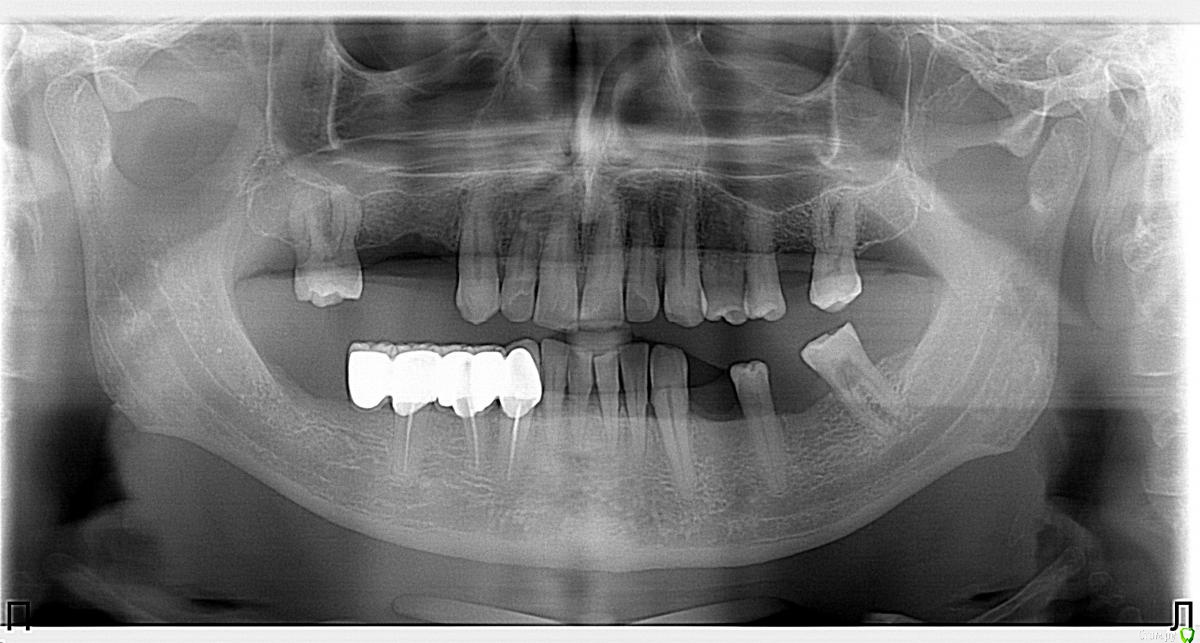

Здравствуйте уважаемые коллеги. Прошу у Вас совета какой план лечения вы бы рекомендовали данному пациенту.

Сразу замечу, я сначала рассматривал вариант с ортодонтией (чтобы собрать все зубы вместе) а далее в отсутствующие места имплантация. Но, пациент не в силах оплатить это лечение. Так как пациент мой бывший учитель, я хочу ему помочь, сделать работу которая материально минимально затратна и функционально его обеспечит.

37ой зуб я уже удалил, сначала сделал ревизию, обнаружен был кариес корня по фуркации, поэтому удалили. На данный момент пациент не может полноценно жевать.

Меня больше смущает 2 момента, 1й - это то что на верхней челюсти зубы "разбросаны" как попало, не знаю что можно сделать не собрав их вместе предварительно. 2ой - в 4ом сегменте мост, консольный, его снимать не хочется, так как его по сути недавно поставили, а не сняв его не знаю что можно сделать в 3ем сегменте, если имплантацию откидываем как вариант....

Если вариант с имплантацией не рассматриваем 100%,то либо бюгеля,либо мосты.В случае НЧ,консольный зуб в крайнем случае можно отпилить,чтоьы не снимать весь мост,сделать мост 33-35 и кламмерный бюгель.На ВЧ аналогично,либо мосты,если 16 рискнете под опору,либо кламмерный бюгель

спасибо за ответ. Я с вами полностью согласен, хороший план, но меня вот беспокоят два момента: 1й - на верхнюю челюсть если сделать бюгель с кламмерами, то в области 24,25 там маленький зазор, а между 25 и 27 там зазор такой, что зуб вроде бы не поместится, в таких случаях там зуб не ставить? просто каркас?

2й момент - слева премоляры вне контакта, если работать под существующий прикус (скорее всего так и будем работать) то они опять останутся без контакта, это не будет проблемой?